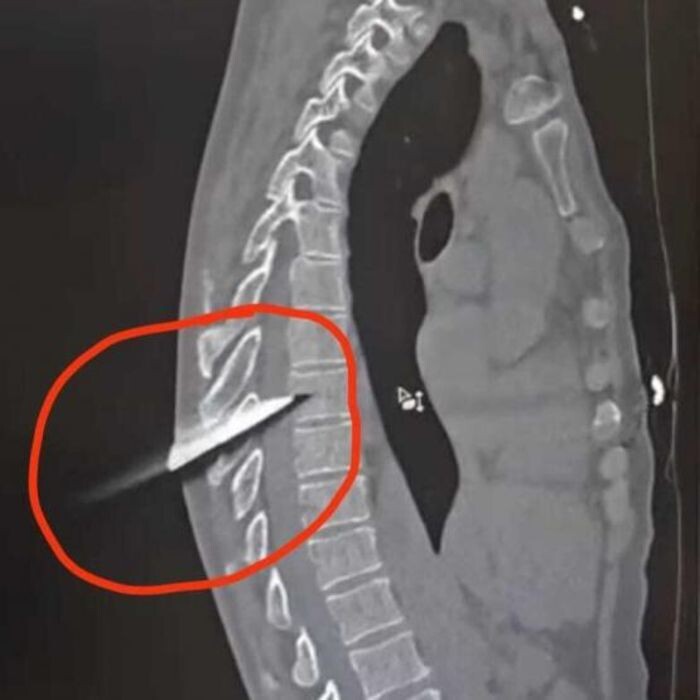

Сообщается, что 15-сантиметровое лезвие прошило пострадавшему позвоночник и задело спинной мозг. Это представляло серьезную угрозу для его жизни и грозило инвалидностью.

Источник фото: Минздрав РО